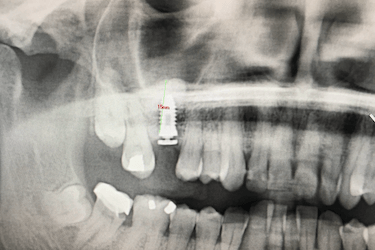

Paciente real del Dr. Ferrer que presenta la ausencia de una pieza dental.

Al no haber sustituido el diente perdido se ha producido una reabsorción ósea que ha provocado una disminución de la altura del hueso maxilar.

Antes del injerto de hueso dental solo había una altura de 5 mm para colocar el implante.

Para que el especialista pueda colocar un implante dental de forma estable y segura, es necesario una altura de hueso maxilar de al menos 8 – 10 mm.

El mismo día de la cirugía el implantólogo realiza una elevación del seno maxilar y posterior injerto de hueso dental artificial.

El odontólogo levanta la membrana del seno maxilar para introducir del material de relleno que aumentará la cantidad y la calidad del hueso del paciente.

Después de la osteointegración del implante, el paciente acude a revisión para ver el estado del hueso artificial injertado.

La altura del hueso maxilar es ahora de 15 mm lo que ha permitido la colocación del implante dental con poco hueso inicialmente.